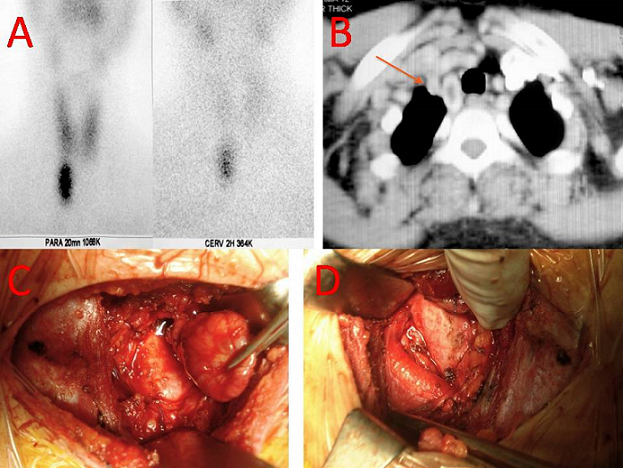

A 46-year-old female with a history of muscle weakness, nephrolithiasis and peptic ulcer. He was found to have hypercalcemia (115 mg/l), hypophosphoremia (16 mg/l) and increased PTH serum level (1090 pg/l). In order to discriminate between PH and pseudohyperparathyroidism, a solid-phase, two site chemiluminescent enzyme-labeled immunometric assay directed towards the intact PTH molecule was used and a diagnosis of primary hyperparathyroidism was made. Several studies were performed with the purpose to achieve a pre-operative localization of the oversecreting parathyroid tumor. A cervical sonography showed a normal thyroid gland and no evidence of the tumor was found in the neck. Therefore a 99-TC sesta MIBI was carried out and an accumulation area projected onto the anterior mediastinum was demonstrated (A). Finally a computed tomography scan of the thorax revealed a 4 cm nodule, in the thymic and paratracheal region of the anterior mediastinum (B). The patient underwent surgical resection of the tumor by a lower cervicotomy approach (C,D). Intraoperative parathyroid hormone measurements show a appropriate decrease in PTH levels. A 4x3x2 cm surgical specimen of a parathyroid tissu mass was removed. The anatomopathological examination confirmed the diagnosis of parathyroid adenoma. The post-operative course was uneventful and the patient was discharged in 4th post-operative day with an excellent functional and cosmetic result. A quarterly follow-up was started. PTH serum level and calcemia have been within normal ranges all through 18 months after surgery.